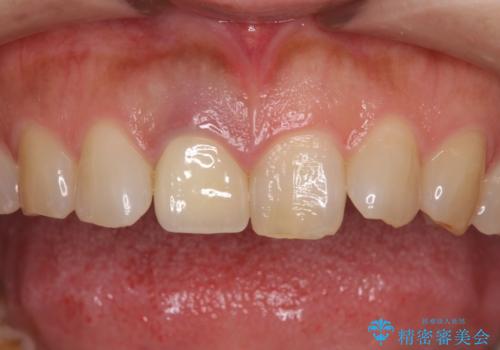

- セラミッククラウンが白すぎる前歯と、放置している奥歯を気にして来院された患者様です。

前歯のセラミッククラウンは将来ホワイトニングをするつもりで白くしたものの、それほど白くならず、ホワイトニングも面倒くさいとのことで白すぎる印象となっていました。

前歯、奥歯ともにオールセラミッククラウンやセラミックインレーにて治療を行うこととしました。

前歯のセラミッククラウンは周りの歯と調和させるためにオーダーメイドタイプのものをおすすめしましたが、元が白すぎていたため、概ね色合いが合えば大丈夫であるとのことで、既製パターンの色調で仕上げました。